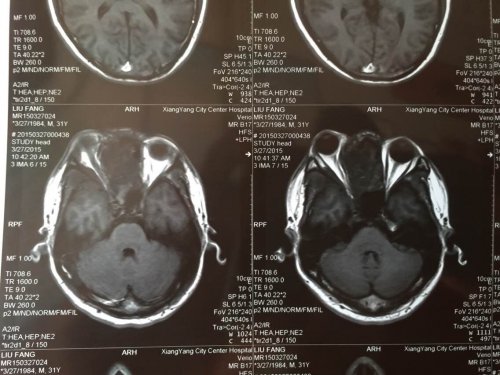

03—27 影像图:

03—27 影像图: